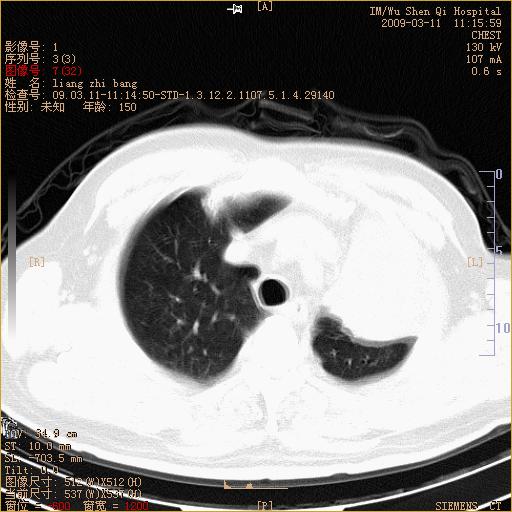

标题: CT18604:男,60岁,咳嗽一月余 [打印本页]

标题: CT18604:男,60岁,咳嗽一月余

1)考虑左肺上叶中央型肺癌并左肺上叶肺不张;建议必要时行纤支镜检查进一步明确诊断。2)左侧胸腔积液。

考虑左肺上叶中央型肺癌并左肺上叶肺不张

肺门肿块、支气管开口闭塞伴肺不张及胸水!典型的中心型肺癌变现!

1、左肺上叶中央型肺癌并上叶阻塞性肺不张。

2、左侧胸腔少量积液,右侧胸膜轻度增厚。

左肺们肿块并左肺上叶不张。考虑左肺中心性肺癌并左肺上叶不张及左侧胸腔积液